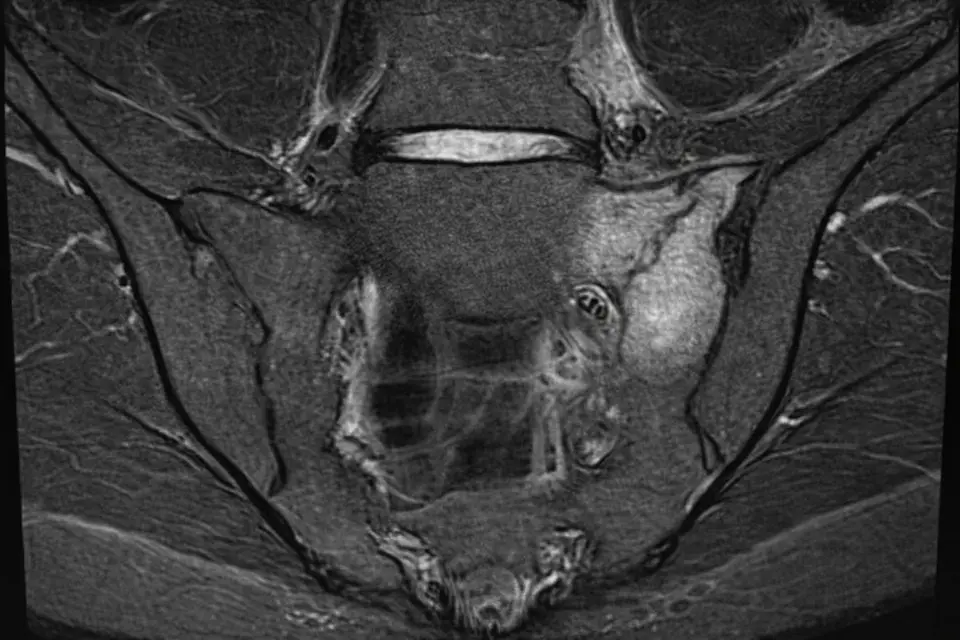

レントゲンでは初期には異常が見つからないことも多いため、MRI検査が早期発見にとても重要です。

必要に応じて、骨の状態を詳しく確認するためにCT検査を行うこともあります。

初期の段階ではレントゲンに異常が映らないことも多いため、必要に応じてMRIなどの検査が行われます。治療は基本的に安静が中心で、運動を続けてしまうと治るまでに時間がかかるため、早めに気づいて適切に休むことが大切です。

MRI検査が有効で、早い段階で見つけることができます。また、ある程度時間が経つと、CT検査で骨の変化を確認できることもあります。

診断にはMRIなどの検査が有効で、早い段階で見つけることができます。